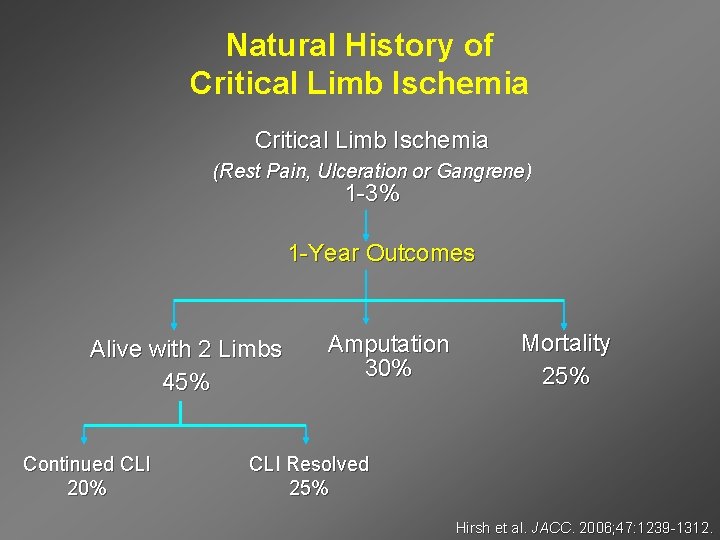

Natural History of Critical Limb Ischemia (Rest Pain, Ulceration or Gangrene) 1 -3% 1 -Year Outcomes Alive with 2 Limbs 45% Continued CLI 20% Amputation 30% Mortality 25% CLI Resolved 25% Hirsh et al. JACC. 2006; 47: 1239 -1312.